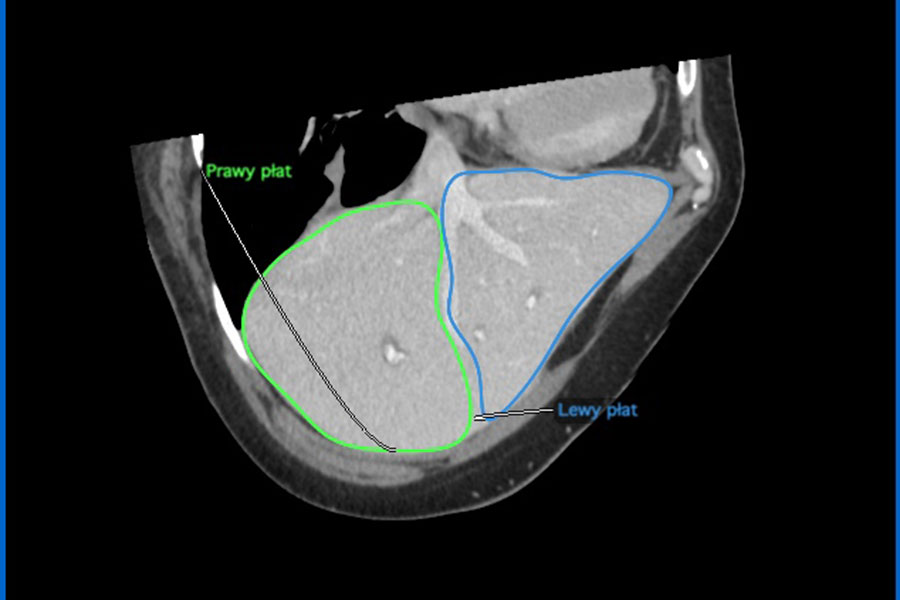

W Klinice Chirurgii Ogólnej, Transplantacyjnej i Wątroby UCK WUM wykonano pierwsze w Polsce przeszczepienie wątroby pobranej od dawcy zmarłego i podzielonej dla dwóch dorosłych biorców. To kolejny kamień milowy w programie transplantologii UCK WUM i kolejna szansa na zwiększenie liczby przeszczepień. Operacja przeprowadzona została przez zespół prof. Michała Grąta i polegała na przeszczepieniu prawej części wątroby dla jednego biorcy i lewej części wątroby dla drugiego biorcy. Rozpoczęcie programu przeszczepiania podzielonych wątrób było ogromnym wyzwaniem medycznym i organizacyjnym, możliwym do podjęcia dzięki doświadczeniu zespołu Katedry i Kliniki Chirurgii Ogólnej, Transplantacyjnej i Wątroby UCK WUM, którą kieruje prof. Grąt w zakresie operacji wątroby i dróg żółciowych. Stopień skomplikowania procedury odzwierciedla liczebność zaangażowanego zespołu: 15 chirurgów, dwóch anestezjologów, radiolog, pięć instrumentariuszek, cztery anestetyczki. Oba fragmenty wątroby podjęły funkcję po przeszczepieniu. Pacjenci są w dobrym stanie, bez powikłań pooperacyjnych.